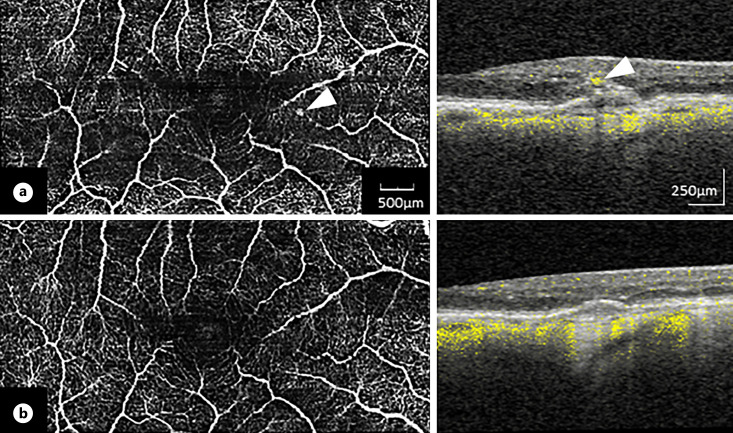

背景:本综述旨在系统总结目前关于老年性黄斑变性(AMD)中 "3型黄斑新生血管"(MNV3)的知识:最近的组织病理学和多模态成像发现促使人们一致定义了AMD的新术语 "3型黄斑新生血管"。MNV3起源于深层血管丛,是一种新生血管过程,初期与视网膜色素上皮细胞没有联系。这种类型具有许多临床和病理形态学特征,有别于 AMD 中的其他两种 MNV。此外,它的发病率似乎也比以前认为的要高。在光学相干断层扫描(OCT)中,MNV3 可分为 1-3 期。视网膜外层的高反射灶可能是前驱病变。此外,MNV3 的特点还包括与网状假皱纹密切相关、双侧发病率高、与高龄和动脉高血压密切相关、脉络膜厚度减少以及绒毛膜血流信号减少。最新的 MNV3 抗血管内皮生长因子(VEGF)研究数据表明,对 OCT 生物标志物视网膜内液和视网膜下液的解释应不同于其他类型。此外,应单独分析 MNV3 眼球的数据,以便将来制定针对特定类型的最佳治疗策略:这篇综述强调了准确描述 nAMD 病变特征和针对 MNV 类型(尤其是 MNV3)的方法的必要性。

Summary: Recent histopathologic and multimodal imaging findings led to the consensus definition of the new term "type 3 macular neovascularization" in AMD. MNV3 originates in the deep vascular plexus as a neovascular process without connection with the retinal pigment epithelium in the initial stages. This type has numerous clinical and pathomorphologic features that separate it from the other two types of MNV in AMD. Besides, its frequency appears to be higher than previously thought. In optical coherence tomography (OCT), MNV3 can be classified into stages 1-3. Hyperreflective foci in the outer retina possibly represent a precursor lesion. In addition, MNV3 is characterized by a strong association with reticular pseudodrusen, a high rate of bilaterality, close associations with advanced age and arterial hypertension, decreased choroidal thickness, and decreased choriocapillaris flow signals. Data from latest anti-vascular endothelial growth factor studies in MNV3 suggest that the OCT biomarkers in intraretinal and subretinal fluids should be interpreted differently than in the other types. Additionally, data from MNV3 eyes should be analyzed separately, allowing optimal type-specific treatment strategies in the future.